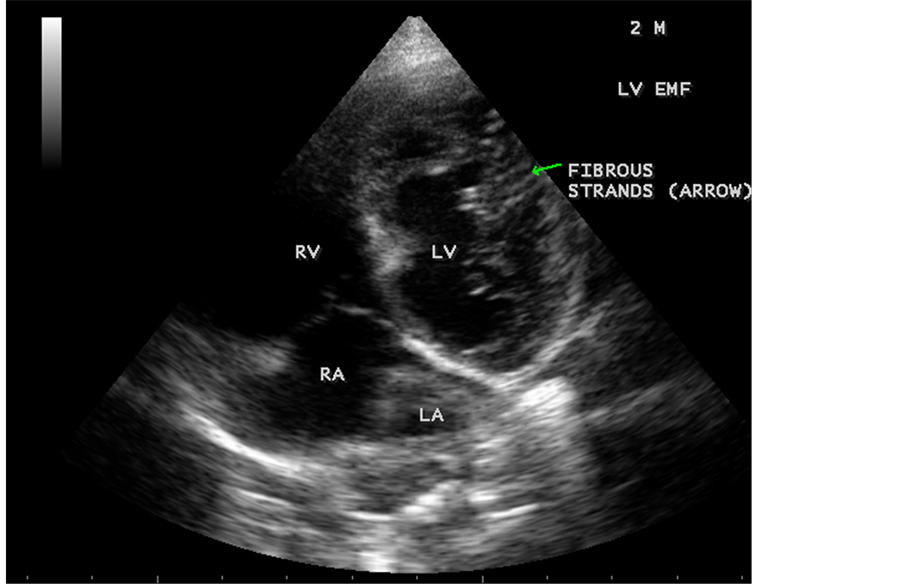

Case 6. Left ventricular endomyocardial fibrosis mimicking as Apical left ventricular hypertrophic cardiomyopathy in a 2-year-old male child as shown in Figure 23, Figure 24 and Figure 25.

Figure 23. Left ventricular endomyocardial fibrosis mimicking as apical left ventricular hypertrophic cardiomyopathy in a 2-year-old male child.

Figure 24. Apical four chamber view showing the endocardial fibrosis of the left ventricle in a 2-year-old male child.

Figure 25. Apical four chamber view showing diffuse endocardial fibrosis of left ventricle in 2-year-old male child.

A left ventricular EMF mimicking apical left ventricular hypertrophic cardiomyopathy as shown in Figure 23, Figure 24 and Figure 25 in a 2-year-old male child and an apical right ventricular hypertrophic cardiomyopathy in a 60-year-old female as shown in Figure 26 mimicking as right ventricular EMF had been found by Transthoracic echocardiographic screening. A right ventricular EMF associated with Psoriasis was shown in Figure 3 to Figure 7 in a 52-year-old male and a left ventricular EMF associated with pemphigus skin lesion in a 63-year-old male as in Figure 40 were detected in this region of Thoothukudi. RV EMF associated with congenital heart diseases such as ostium secundum atrial septal defect in a 26-year-old female antenatally (Primi with 9 months amenorrhea) as shown in Figure 49 and Figure 64 to Figure 66 in a 9-year- old girl. RV EMF associated with RV outflow tract disease (“Double chambered right